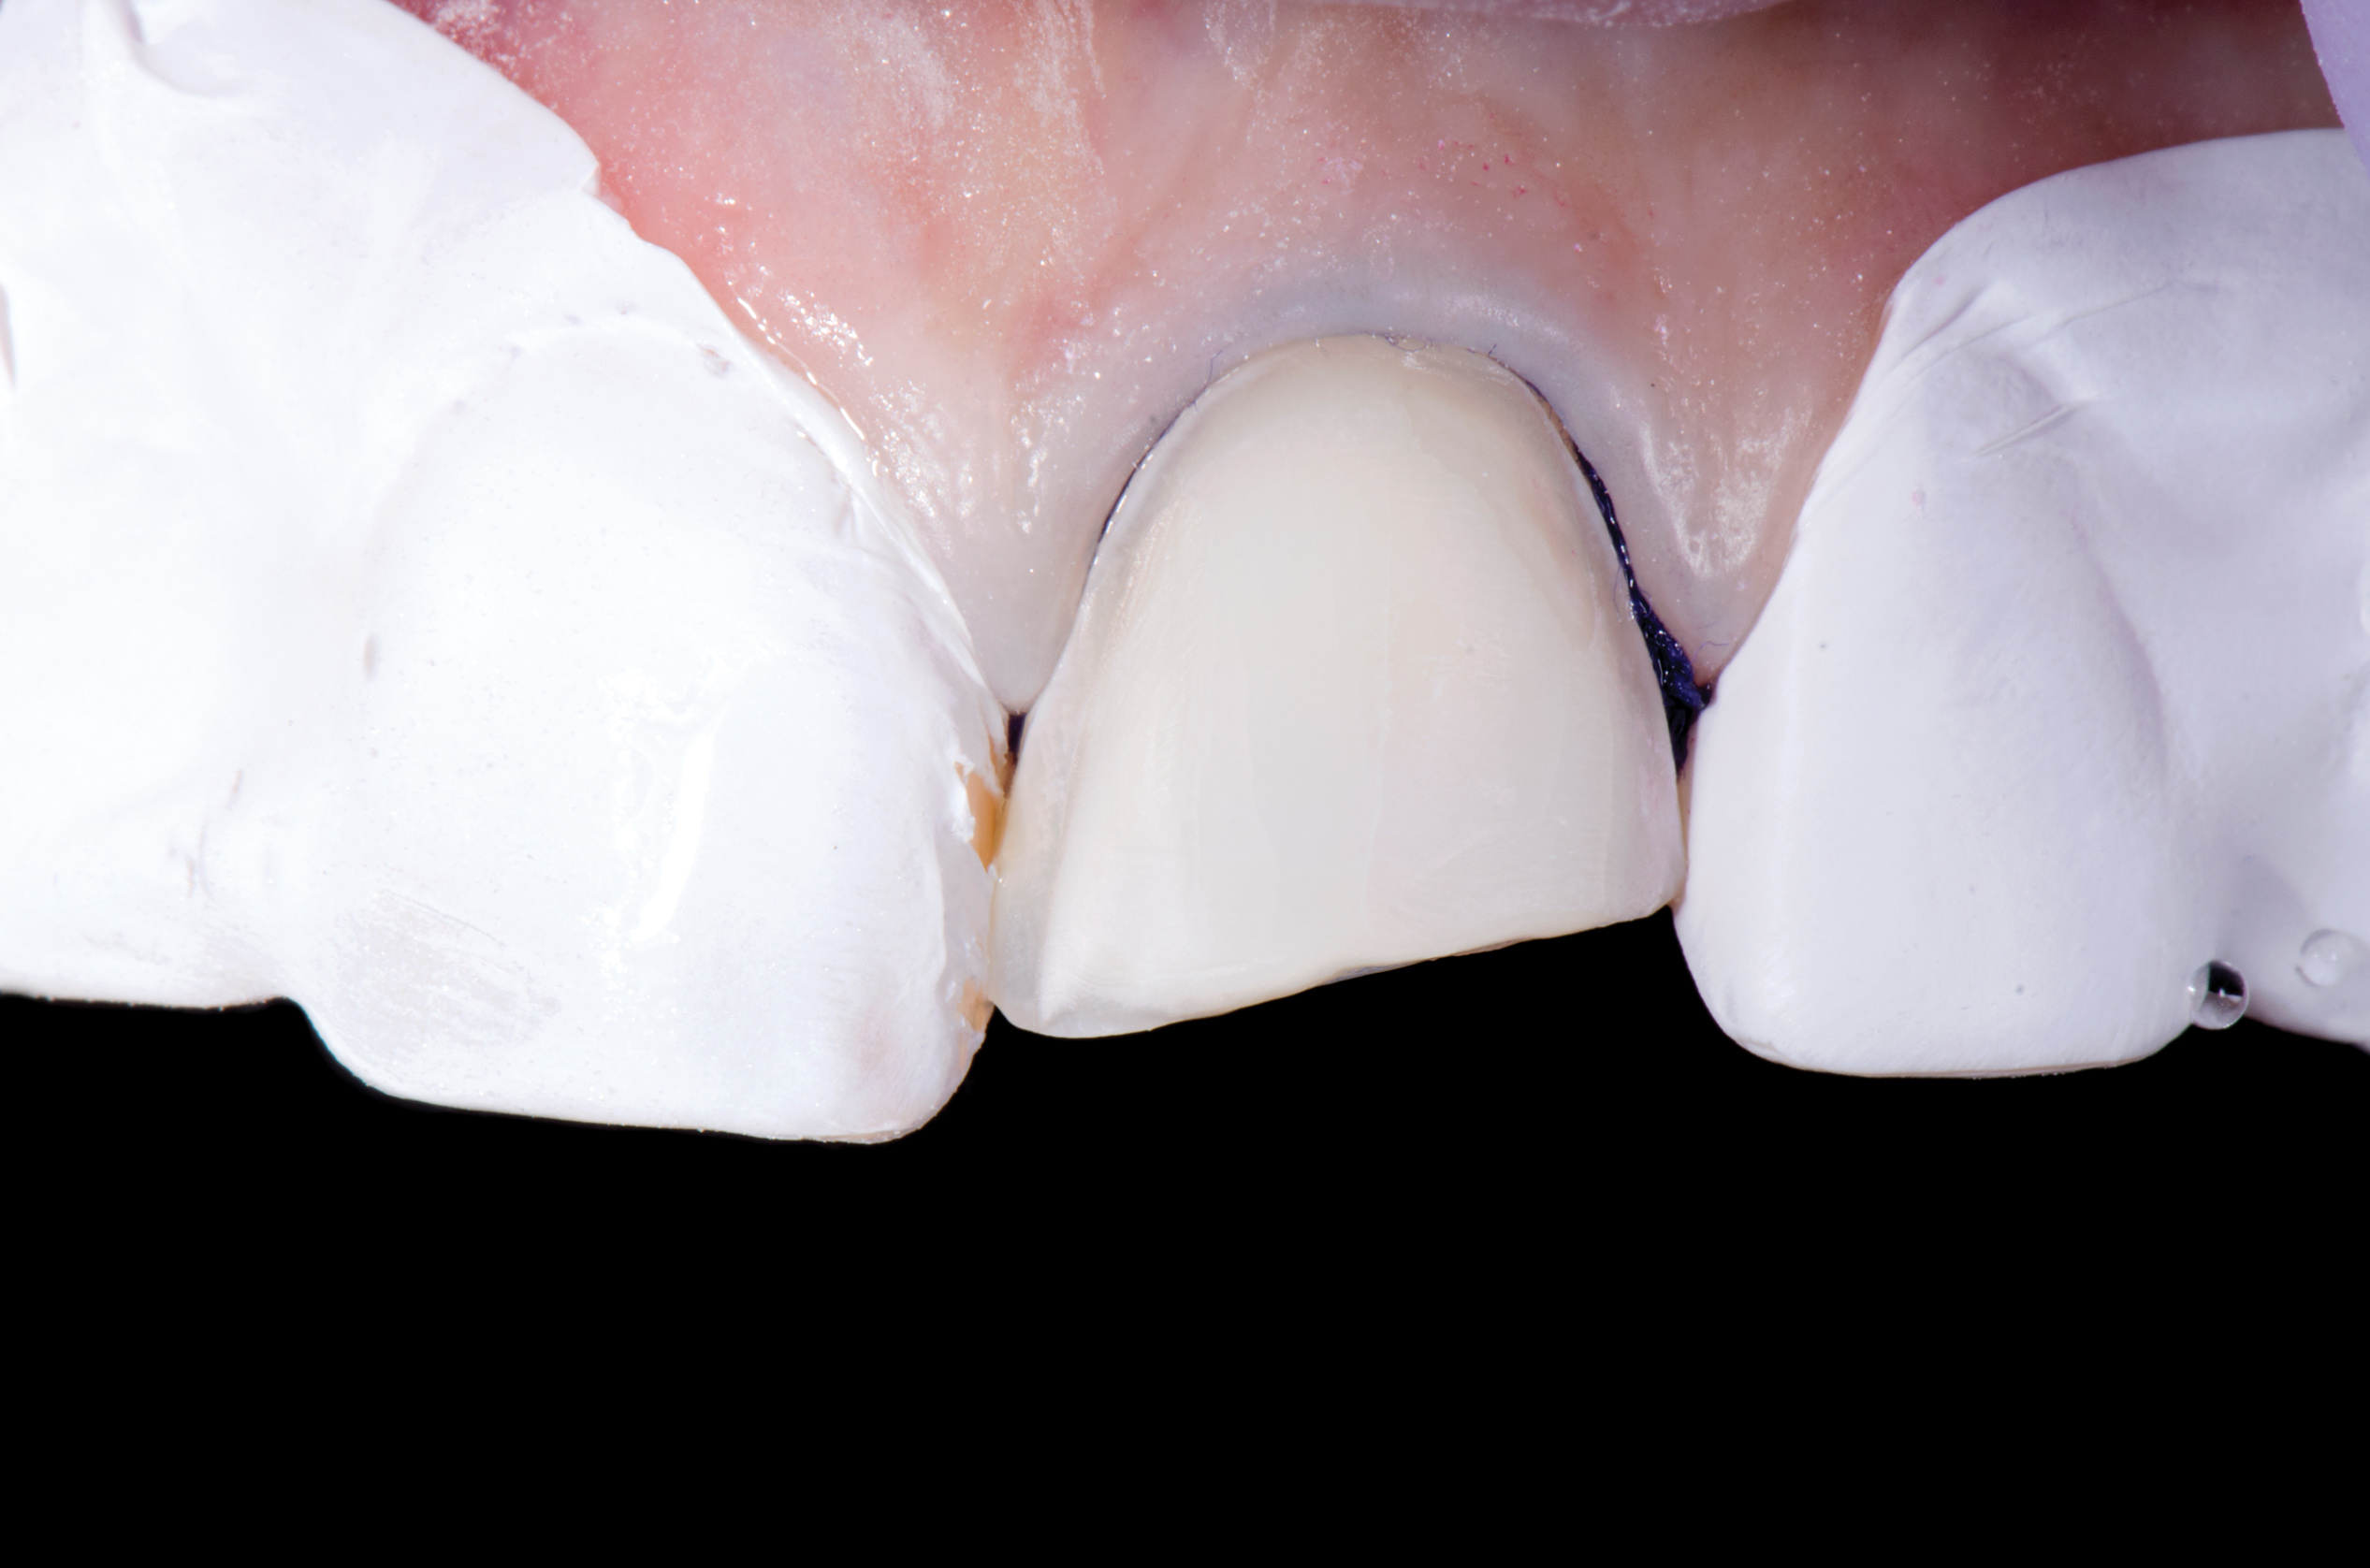

Air abrasion with aluminum trihydroxide has been used as an adjunctive for tooth preparation to remove plaque, light calculus, undermined enamel, poorly bonded resins or liners, and soft-tissue tags prior to bonding. The rationale of biofilm removal before bonding is to remove any impediments to effective etching of enamel that may lead to reduced bond strength and microgaps that could contribute to future stain and leakage. Because biofilm can be difficult to visualize, a one-time application of a two-tone disclosing solution to dried teeth may help reveal biofilm and provide a visual cue for effective removal (Figure 17 through Figure 19). Some cleaning particles other than glycine or sodium bicarbonate can alter the enamel surface; therefore, reapplication of disclosing solution should be avoided as this may lead to risk of undesired staining of tooth structure.

Fig 17. Application of two-tone disclosing solution to reveal biofilm.

Figure 17

Fig 18. Air abrasion with aluminum trihydroxide to remove biofilm.

Figure 18

Fig 19. Cleaned tooth surfaces after air abrasion prior to application of adhesive bonding resin composite to close black triangles.

Figure 19